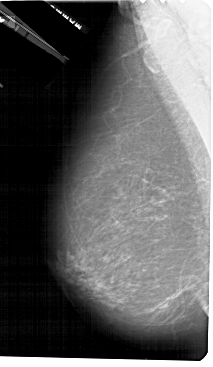

A_1426_1.LEFT_CC

LEFT_CC LINES 5491 PIXELS_PER_LINE 3046 BITS_PER_PIXEL 12 RESOLUTION 43.5 NON_OVERLAY

FILE: A_1426_1.RIGHT_CC.OVERLAY

TOTAL_ABNORMALITIES 1

ABNORMALITY 1

LESION_TYPE MASS SHAPE OVAL MARGINS ILL_DEFINED

ASSESSMENT 4

SUBTLETY 4

PATHOLOGY BENIGN

TOTAL_OUTLINES 1

BOUNDARY